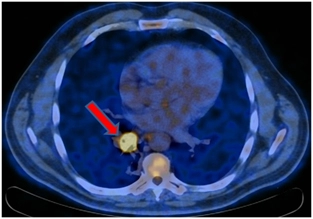

ПЭТ/КТ от 31.05.2017. Отмечается положительная динамика в виде нивелирования центрально расположенного образования нижней доли правого легкого и медиастинального лимфоузла. Постлучевой фиброз, ателектаз нижней доли правого легкого. Умеренно выраженный правосторонний гидроторакс. Повышение метаболизма в кардиальном отделе пищевода – постлучевой воспалительный процесс.